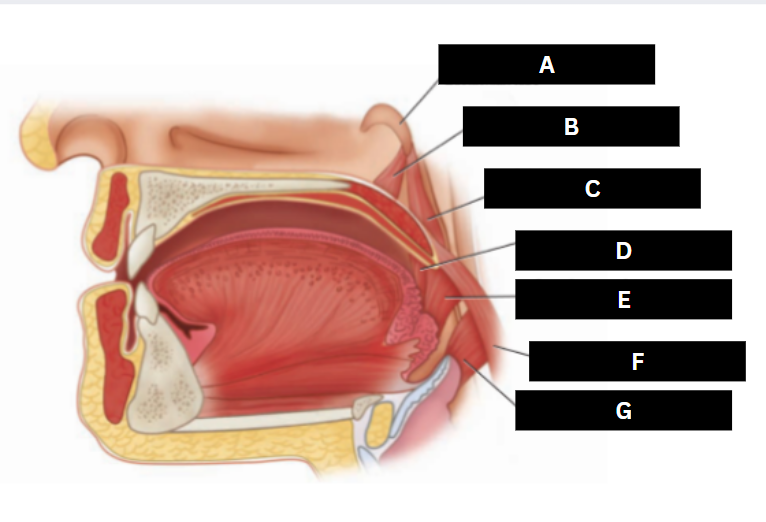

Eustachian tube

A

Levator veli palatini

B

Salpingopharyngeus

C

Palatoglossus

D

Superior pharyngeal constrictor

E

Palatopharyngeus

F

Middle pharyngeal constrictor

G